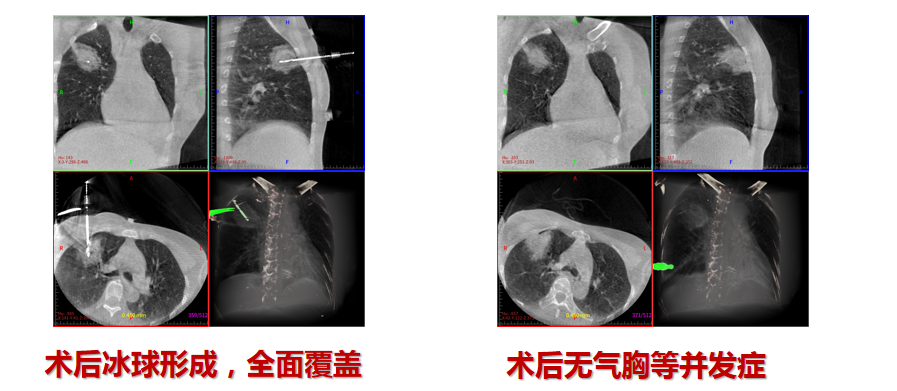

氩氦刀消融

4. **高效微创**:局部麻醉下1小时内完成手术,术后仅留针眼大小创口,患者当日即可下床活动。

- **氩氦刀精准控温**:在影像引导下,冷冻消融完全灭活结节,最大限度保护周围正常肺组织。